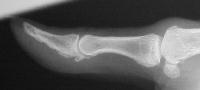

Comparison views of the opposite side: